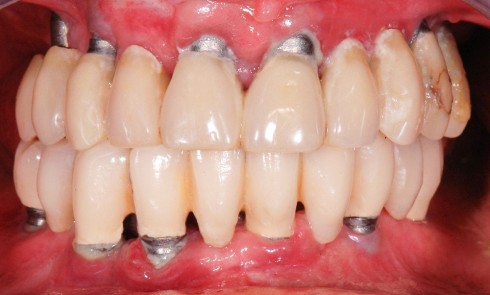

Contexte clinique et objectifs Une patiente partiellement édentée mandibulaire se présente avec les dents 33, 35, 36 et 43 compromises (alvéolyse...